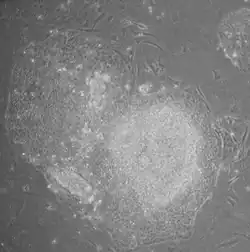

iPSC derivation is typically a slow and inefficient process, taking one–two weeks for mouse cells and three–four weeks for human cells, with efficiencies around 0.01–0.1%. However, considerable advances have been made in improving the efficiency and the time it takes to obtain iPSCs. Upon introduction of reprogramming factors, cells begin to form colonies that resemble pluripotent stem cells, which can be isolated based on their morphology, conditions that select for their growth, or through expression of surface markers or reporter genes.

- Morphology: iPSCs were morphologically similar to ESCs. Each cell had round shape, large nucleolus and scant cytoplasm. Colonies of iPSCs were also similar to that of ESCs. Human iPSCs formed sharp-edged, flat, tightly packed colonies similar to hESCs and mouse iPSCs formed the colonies similar to mESCs, less flat and more aggregated colonies than that of hESCs.